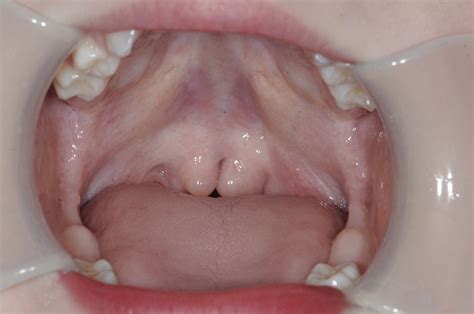

The condition is typically characterized by a triad of features often referred to by clinicians as the "classic triad":

• Bifid uvula: The uvula (the small piece of tissue hanging in the back of the throat) appears split or notched.

• Zona pellucida: A thin, bluish, or translucent area in the middle of the soft palate where the muscle is missing.

• Palpable notch: A small indentation or "V" shape can be felt at the junction between the hard and soft palates.